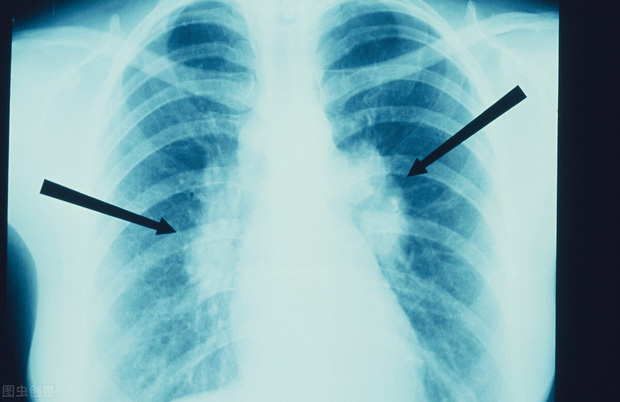

Khi đó, sau một đợt ho liên tục kéo dài và không thuyên giảm dù đã dùng nhiều loại thuốc khác nhau, ông Lu Tongfang cuối cùng đã đến bệnh viện để khám. Qua các xét nghiệm hình ảnh và giải phẫu bệnh, cuối cùng ông được chẩn đoán mắc bệnh ung thư biểu mô tuyến ở phổi giai đoạn cuối.

Dù vậy, chỉ sau 2 năm, vận đen lại ập đến. Tháng 5/2019, cha mẹ của ông Lu Tongfang tình cờ phải nhập viện do bị cảm nặng. Khi kiểm tra, bác sĩ phát hiện bố mẹ ông có bóng mờ rõ ràng trong phổi, nghi là ung thư phổi.

Sau hàng loạt xét nghiệm, kết luận cuối cùng đúng là như vậy. Điều này khiến ông Lu Tongfang không thể tin được, cha mẹ ông tuy đã già nhưng không bao giờ hút thuốc, uống rượu, cơ thể luôn dẻo dai, tại sao lại mắc bệnh ung thư? May mắn thay, khối u phổi của cha mẹ ông vẫn còn ở giai đoạn đầu, phẫu thuật có hy vọng chữa khỏi rất lớn.

Tìm hiểu bệnh sử, bác sĩ được kể về trường hợp bệnh của ông Lu Tongfang 2 năm trước thì ngay lập tức đề nghị vợ ông cũng nên đi khám. Lúc này, bác sĩ phát hiện ra rằng mặc dù vợ của ông Lu Tongfang không bị ung thư nhưng lại có nhiều nốt ở cả hai phổi. Vì các nốt ác tính thuộc loại ung thư phổi giai đoạn đầu nên sau khi được bác sĩ kiểm tra cẩn thận, một số nốt có thể có độ ác tính cao đã được loại bỏ.